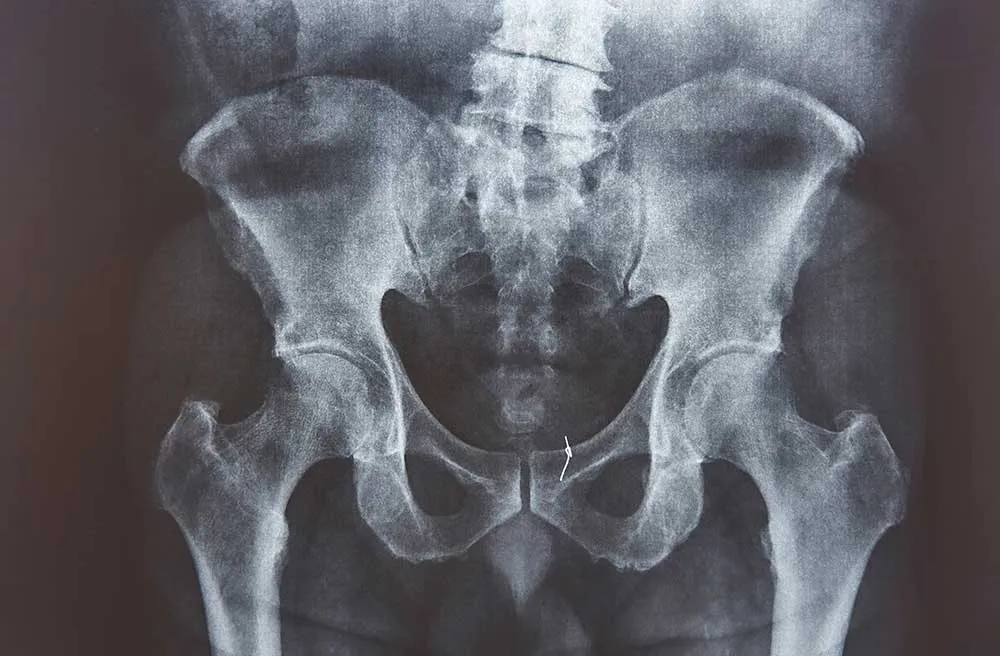

What is Hip Osteoarthritis?

Hip osteoarthritis is a condition where the cartilage in the hip joint wears away, leading to pain and stiffness. It can affect your ability to walk and perform daily activities. Mr. Turab Syed provides comprehensive care for hip arthritis, including joint preservation and replacement surgery.